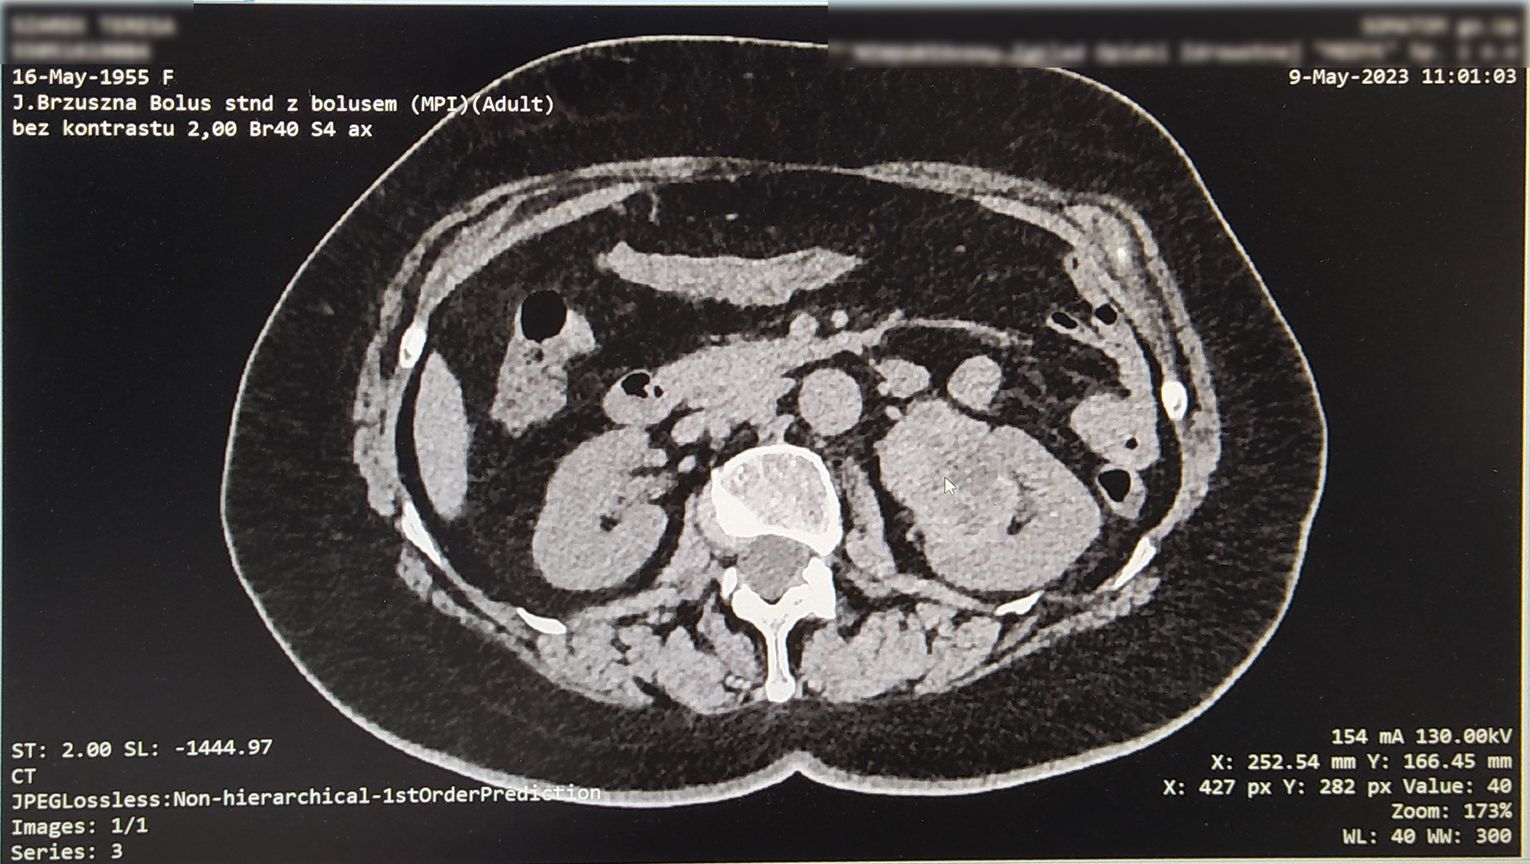

Pierwszy z pacjentów, to blisko 70-letni mężczyzna. Od lat walczył z otyłością, lecz mimo wielu prób nie udawało mu się jej pokonać. Zgłosił się do lekarza i dopiero w pogłębionej diagnostyce przeprowadzonej w kozielskiej lecznicy wykryto rozległą patologiczną zmianę w obrębie nerki. Guz utrudniał już znacznie normalne funkcjonowanie spychając pozostałe narządy w jamie brzusznej. Podjęto decyzję o natychmiastowej operacji metodą nie laparoskopową, a klasyczną, z uwagi na objętość i charakter umiejscowienia zmiany. Po 2,5-godzinnej operacji usunięto zmianę, której dokładne badania przeprowadzają obecnie histopatolodzy. Lekarze wstępnie określili zmianę jako wodonerczowo-guzowatą. Warto dodać, że objętość tego ogromnego guza to ok. 13 litrów, przy poprawnej objętości nerki ok. 300~500 ml. Zabieg zakończył się sukcesem, a pacjent czuje się bardzo dobrze i obecnie nie wymaga już leków przeciwbólowych.